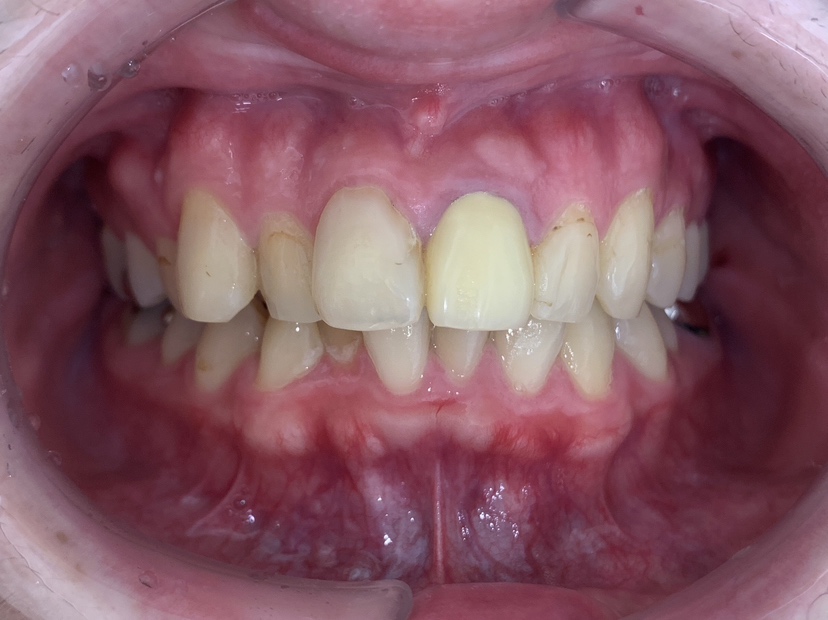

拝見したところ、上下の前歯が前後に重なり合っている「叢生(そうせい)」で、部分的に歯がねじれている「捻転(ねんてん)」がありました。

右上の前歯(側切歯/2番)が内側にずれて生えているため、隣の前歯(犬歯/3番)が飛び出ているようにみえる状態でした。